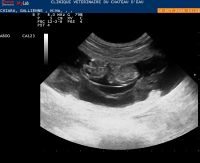

• Diagnostic de gestation (échographie et radiographie)